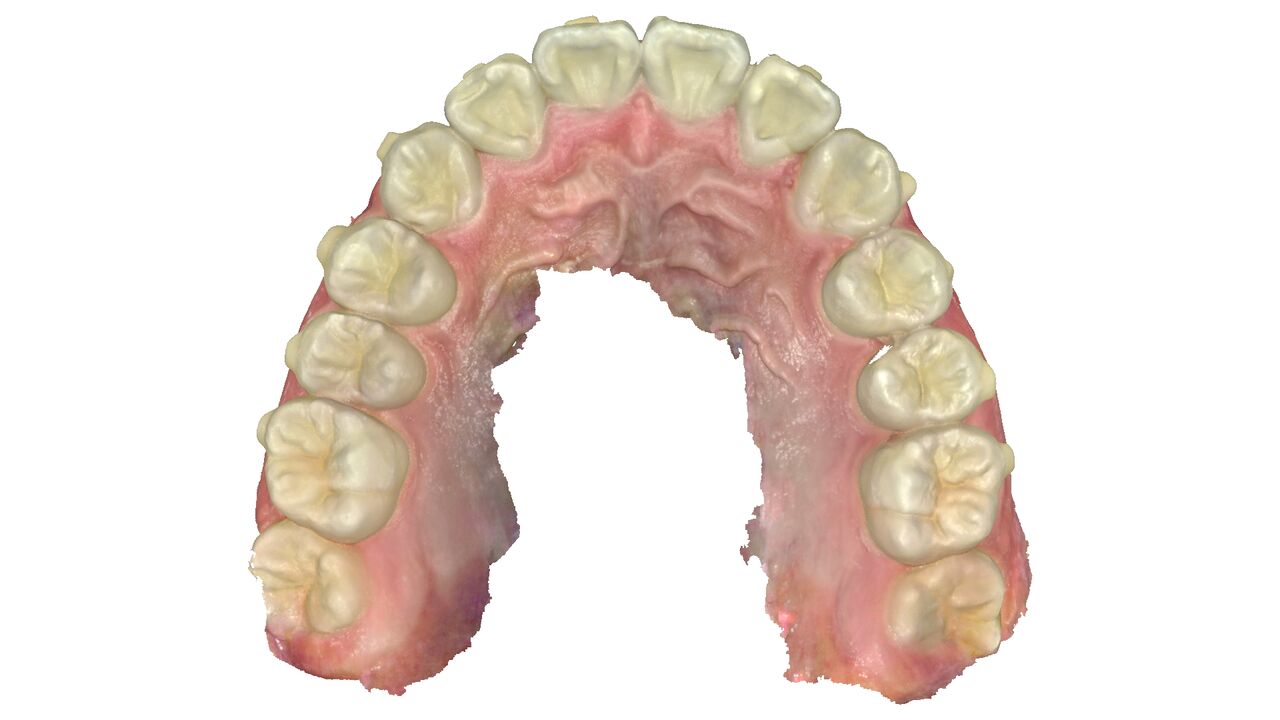

上の歯。前歯に内側に引っ込んだ歯がある。

上の歯。引っ込んだ歯が歯並びの中に納まっている。

上の歯の比較